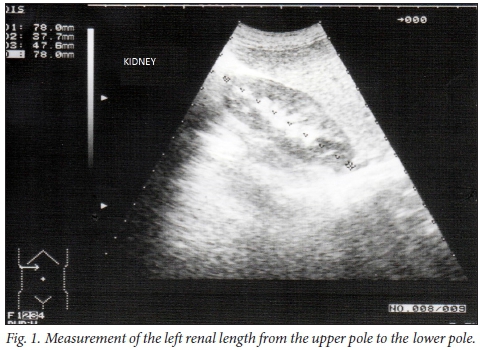

Ultrasonography was performed using an ultrasound unit with a 3.5 MHz convex transducer. RL measurements were performed in the sagittal plane, with children in the supine position. The distance between the top and bottom poles of both kidneys was measured (Fig. 1).